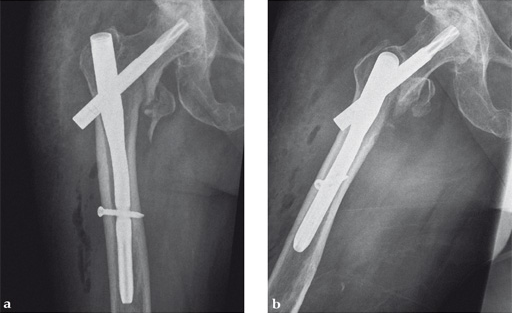

Case 1:

47-year-old female, slipped and fell down the stairs. Traumatic, single 31-A2.1 fracture treated with PFNA.